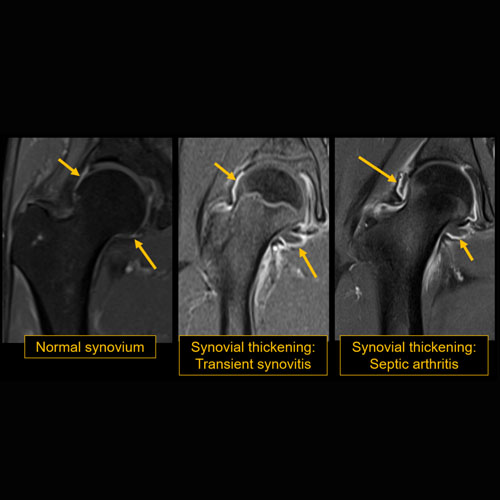

There is a joint effusion or synovitis. [Yes/No]